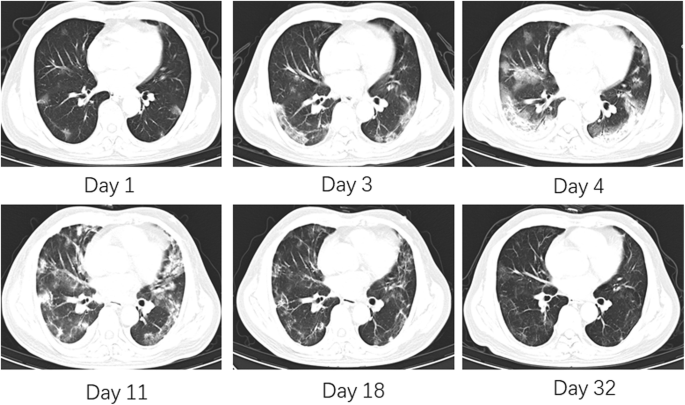

As shown in Fig. 1, on day 4 after CP transfusion, the lactic acid and CRP levels remained high (2.1 mmol/L and 73.23 mg/L, respectively). The arterial oxyhemoglobin saturation (SaO2) decreased to 86%, while the OI decreased to 76 mmHg, and mechanical ventilation was administered. His temperature returned to normal and the OI ascended above 300 on day 11, after which the ventilator was withdrawn. On day 11 after CP transfusion, the RNA test remained positive in throat swab, and CT revealed severe pulmonary lesions (Fig. 2).